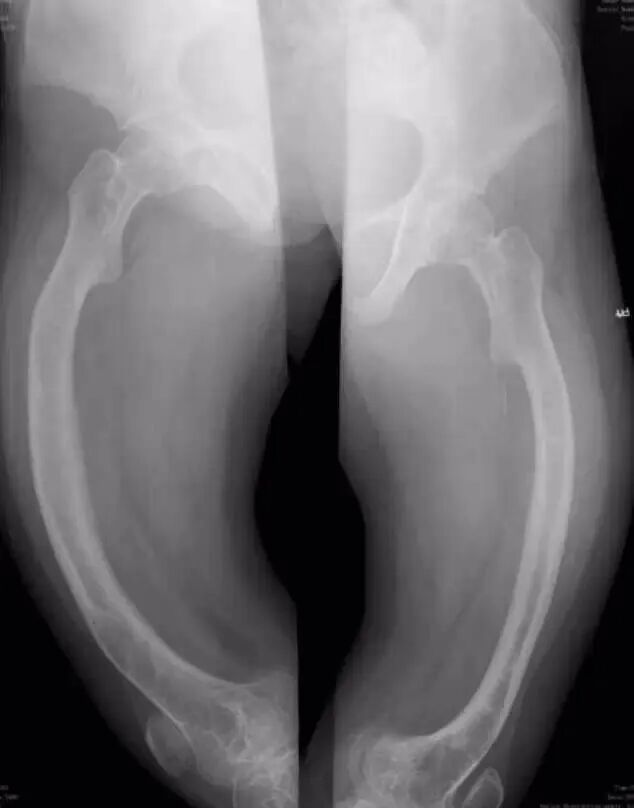

OI标志性特征是骨质脆弱反复骨折, 典型骨骼X线表现(见图二);成骨不全症的临床表现不仅限于骨骼,还常常累及其他结缔组织如眼、耳、皮肤、牙齿等(见图三)。根据临床表型, 澳洲悉尼大学的Sillence教授将OI 分成至Ⅰ-Ⅳ型[7]: Ⅰ型病情最轻, 最常见; Ⅱ最重, 通常围产期致死; Ⅲ型是存活者中最严重的, 常常身材矮小, 呈进行性骨骼畸形; Ⅳ型严重度介于Ⅰ型与Ⅲ型之间。近期发现的Ⅴ型OI 具有肥厚性骨痂、桡骨头脱位、前臂骨间膜钙化、桡骨干骺端下密集骺线等独特临床表现(见图四)。

图二:成骨不全症典型的X线表现

a.股骨干侧位片显示双侧非对称的股骨前弓弯曲愈合中的骨折(实心箭头)和已经愈合的骨折(空心箭头)

b. 胫骨侧位片显示双侧胫骨向前弯曲以及骨折愈合的不同阶段:早期愈合(实心箭头),进行性愈合中(空心箭头),已经愈合(三角);双侧胫骨呈现铅笔样畸形,尤其是腓骨及蜂巢状髓腔,特别是胫骨远端。

c. 骨盆平片显示严重的股骨近端髋内翻畸形以及基本完全愈合的转子下骨折;骨折愈合一般从内侧(压应力侧)开始,而骨折不愈合通常发生外侧表面(张应力侧);

d. 胸腰段脊柱侧位片显示椎体及附件广泛骨质疏松,椎体呈双凹征(空心箭头),扁平椎(实心箭头)以及各种程度的椎体前方楔形变,总的来说成骨不全患者脊柱骨骼改变与生长激素替代治疗的骨骼改变表现非常类似,骨硬化与骨吸收相互交错;